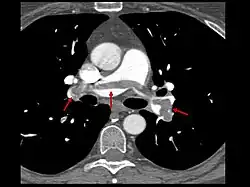

- Le scanner spiralé des artères pulmonaires[13] ou angioscanner des artères pulmonaires : un produit de contraste iodé est injecté en intraveineux. Le mouvement rotatif et longitudinal (caractère spiralé) de la tête du scanner permet de bien visualiser les artères pulmonaires proximales et moyennes et un peu moins bien leur distalité. C’est un excellent examen de diagnostic positif et de gravité, même si les risques liés à l’emploi de produits iodés et la radiation persistent. Il est moins invasif que l'angiographie conventionnelle. Il permet aussi l'évaluation de plusieurs autres structures intrathoraciques (aorte et médiastin, poumon, plèvre), en plus de l'évaluation des artères pulmonaires. Il est considéré souvent comme le nouvel examen de référence.